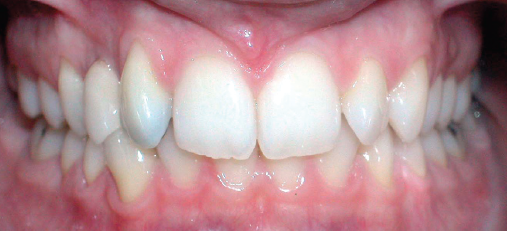

Class I Non-Extraction |